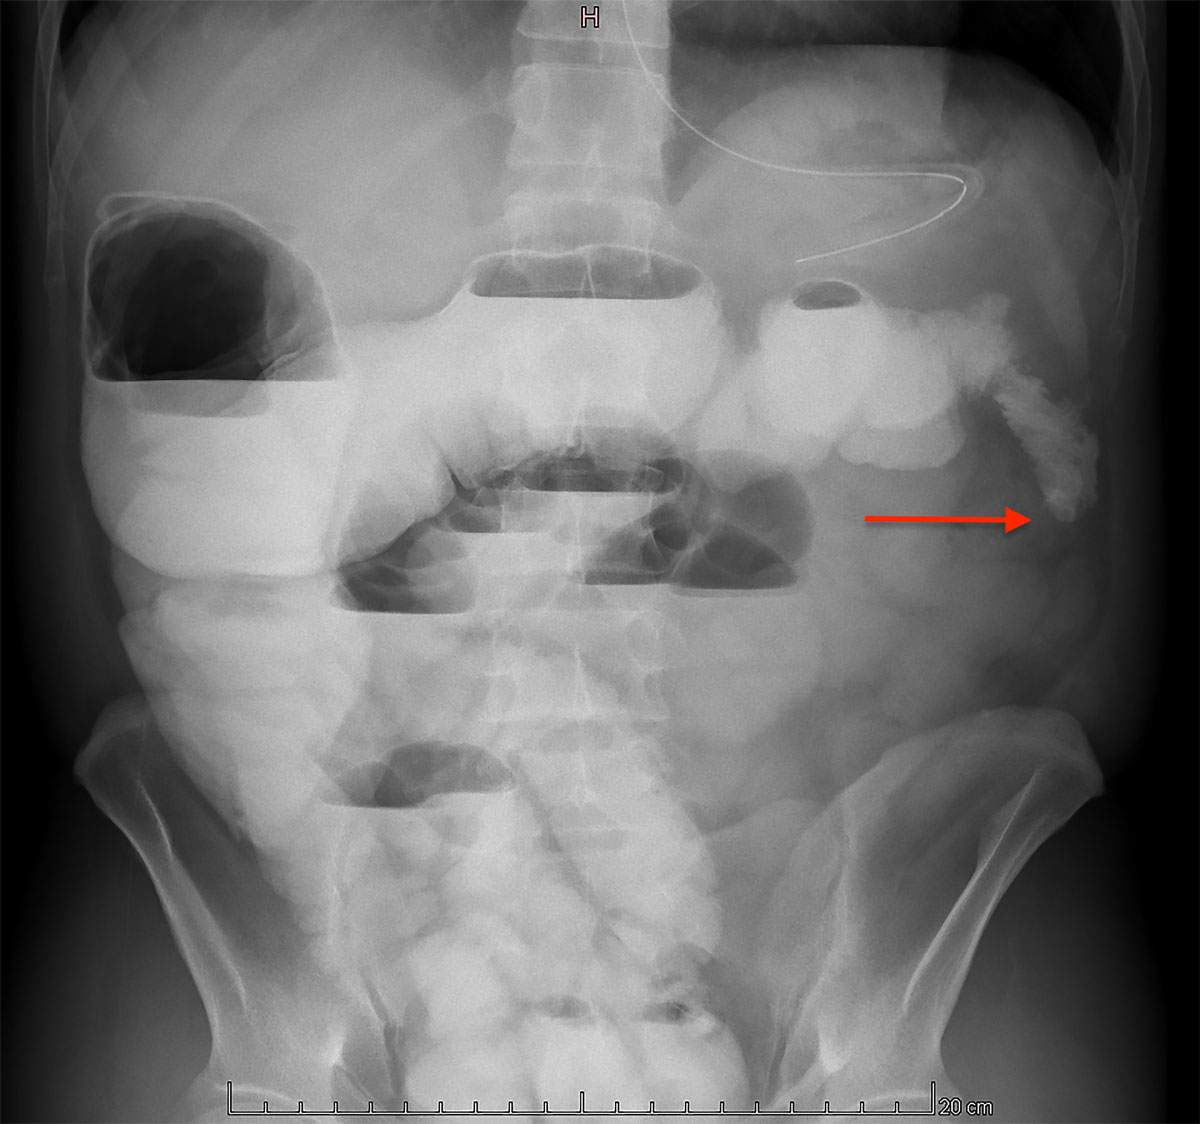

Following the procedure, the patient was admitted to the intensive care unit until postoperative day 1. The postoperative course was uneventful until day 14, when the patient developed signs of ileus. A conservative approach, with fasting and nasogastric tube decompression, failed to improve the clinical course. Radiological investigations revealed a left colonic stenosis (fig. 5), probably due to arterial ligation.

Figure 5 Abdominal radiography with oral contrast showing a left colonic stenosis (arrow).